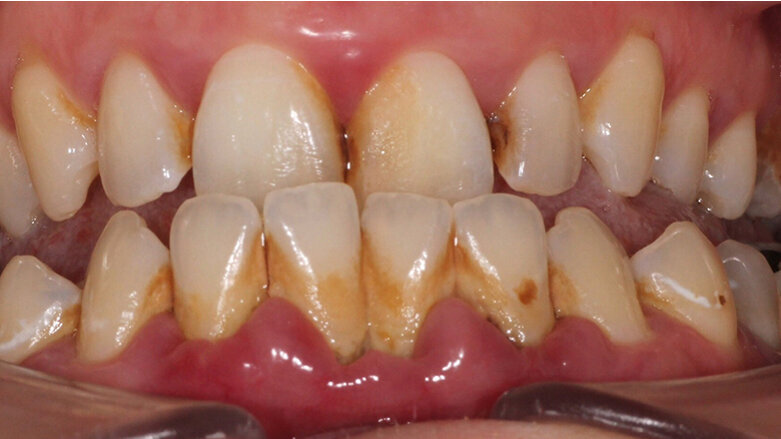

Clinically, the patient presented with plaque accumulation on all surfaces, heavy supraand sub-gingival calculus deposits, florid gingivitis, moderate to severe pocketing and bleeding on probing in all sextants, with spontaneous bleeding in the lower anterior sextant. Significant fetor oris was also noted at the initial consultation.

Upper – Initial presentation. Lower – 8 Weeks later

Treatment Appointment 1 In line with the GBT protocol, disclosing solution was applied and initial assessments, which included plaque and bleeding indices, were carried out; both were recorded at 100%.

Appointment 3 (8 weeks later) The patient was again disclosed, and plaque and bleeding scores were taken. Both scores were recorded as <10% and a dramatic difference in appearance was noted. At this stage, a full-mouth periodontal chart was recorded. Anterior sextants showed no pockets >4mm and posterior sextants showed some shallow residual pocketing interdentally of between 4mm and 5mm with 3 sites measuring 6mm, one of which had bleeding on probing.